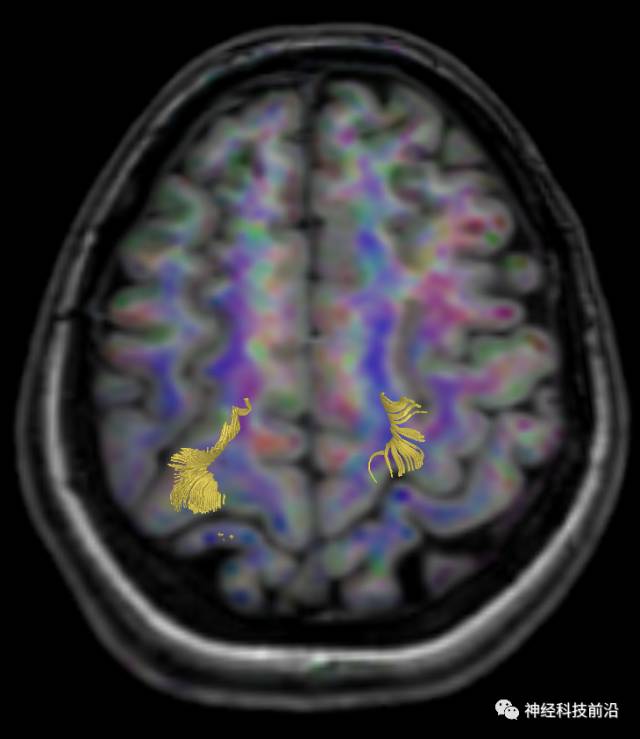

终上所述:脑干高信号为一近环形纤维束,内囊后肢高信号为皮质脑桥束,皮质脊髓束在中脑位置略靠后。高信号位于中脑前缘,是皮质脑桥束的位置所在,另外有部分桥连纤维。